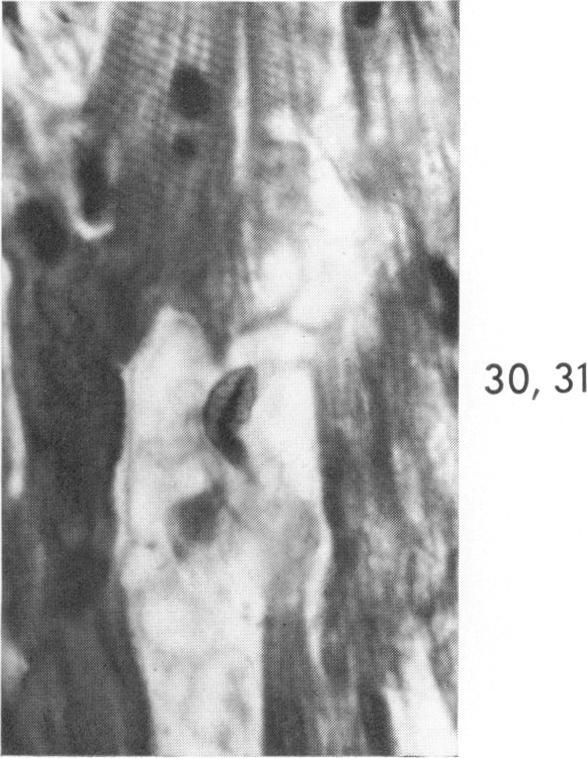

Occurrence of caterpillar nuclei within normal immature and normal appearing and altered mature heart muscle cells and the evolution of Anitschkow cells from the latter.

Am J Pathol. 1966 Jun;48(6):931-57.